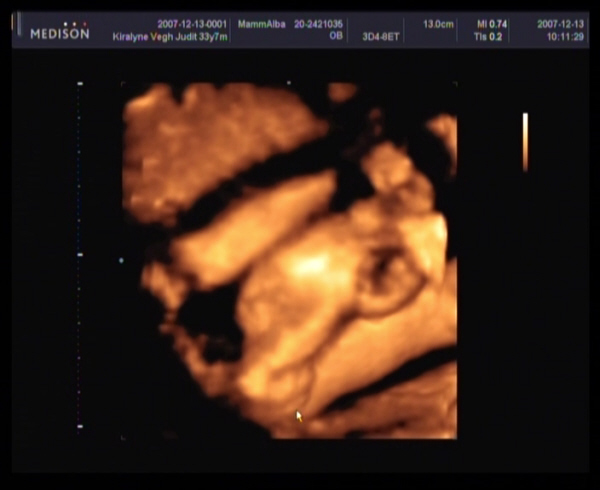

Judy,

gyere a képekkel!!!! Nagyon kíváncsi vagyok Barbikára!!!!!